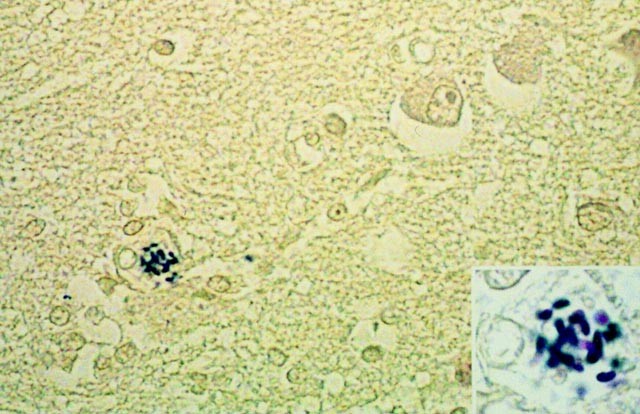

A glial cell containing Gram-positive spores in a cortical brain section. Note the absence of any sign of associated lesions. (AFIP modified Brown Brenn Gram, original magnification, 400×. Inset, original magnification, 1000×.)